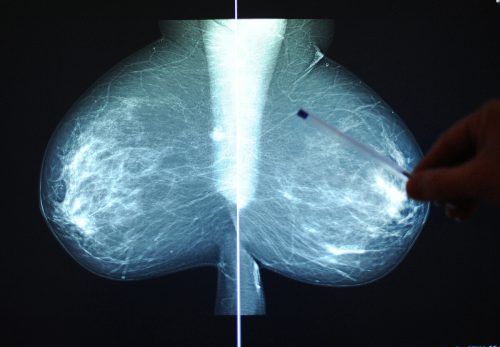

Die Initiative „discovering hands Österreich“ setzt bei der Brustkrebsvorsorge auf den Tastsinn von blinden Frauen. apa

Die Wirksamkeitsstudie zur Brustkrebsfrüherkennung wurde vom Gesundheitsministerium genehmigt.

Wien Die Initiative „discovering hands Österreich“ setzt bei der Brustkrebsvorsorge auf den ausgeprägten Tastsinn von blinden oder sehbehinderten Frauen. Während diese Form der Früherkennung in Deutschland bereits etabliert ist, musste hierzulande diese Methode der Tastuntersuchung erst anerkannt we